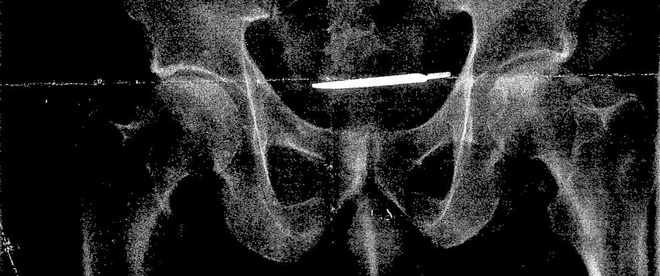

Sau đó, họ lại chụp X-quang cho người đàn ông này, và phát hiện ra... một chiếc dao mổ đang yên vị trong cơ thể ông Turner.

Con dao mổ đã nằm trong bụng ông Glenford Turner bốn năm.

Các bác sĩ xác nhận đây là một dụng cụ mổ còn sót lại trong ca phẫu thuật tiền liệt tuyến cho ông Turner tại bệnh viện West Haven VA vào năm 2013.